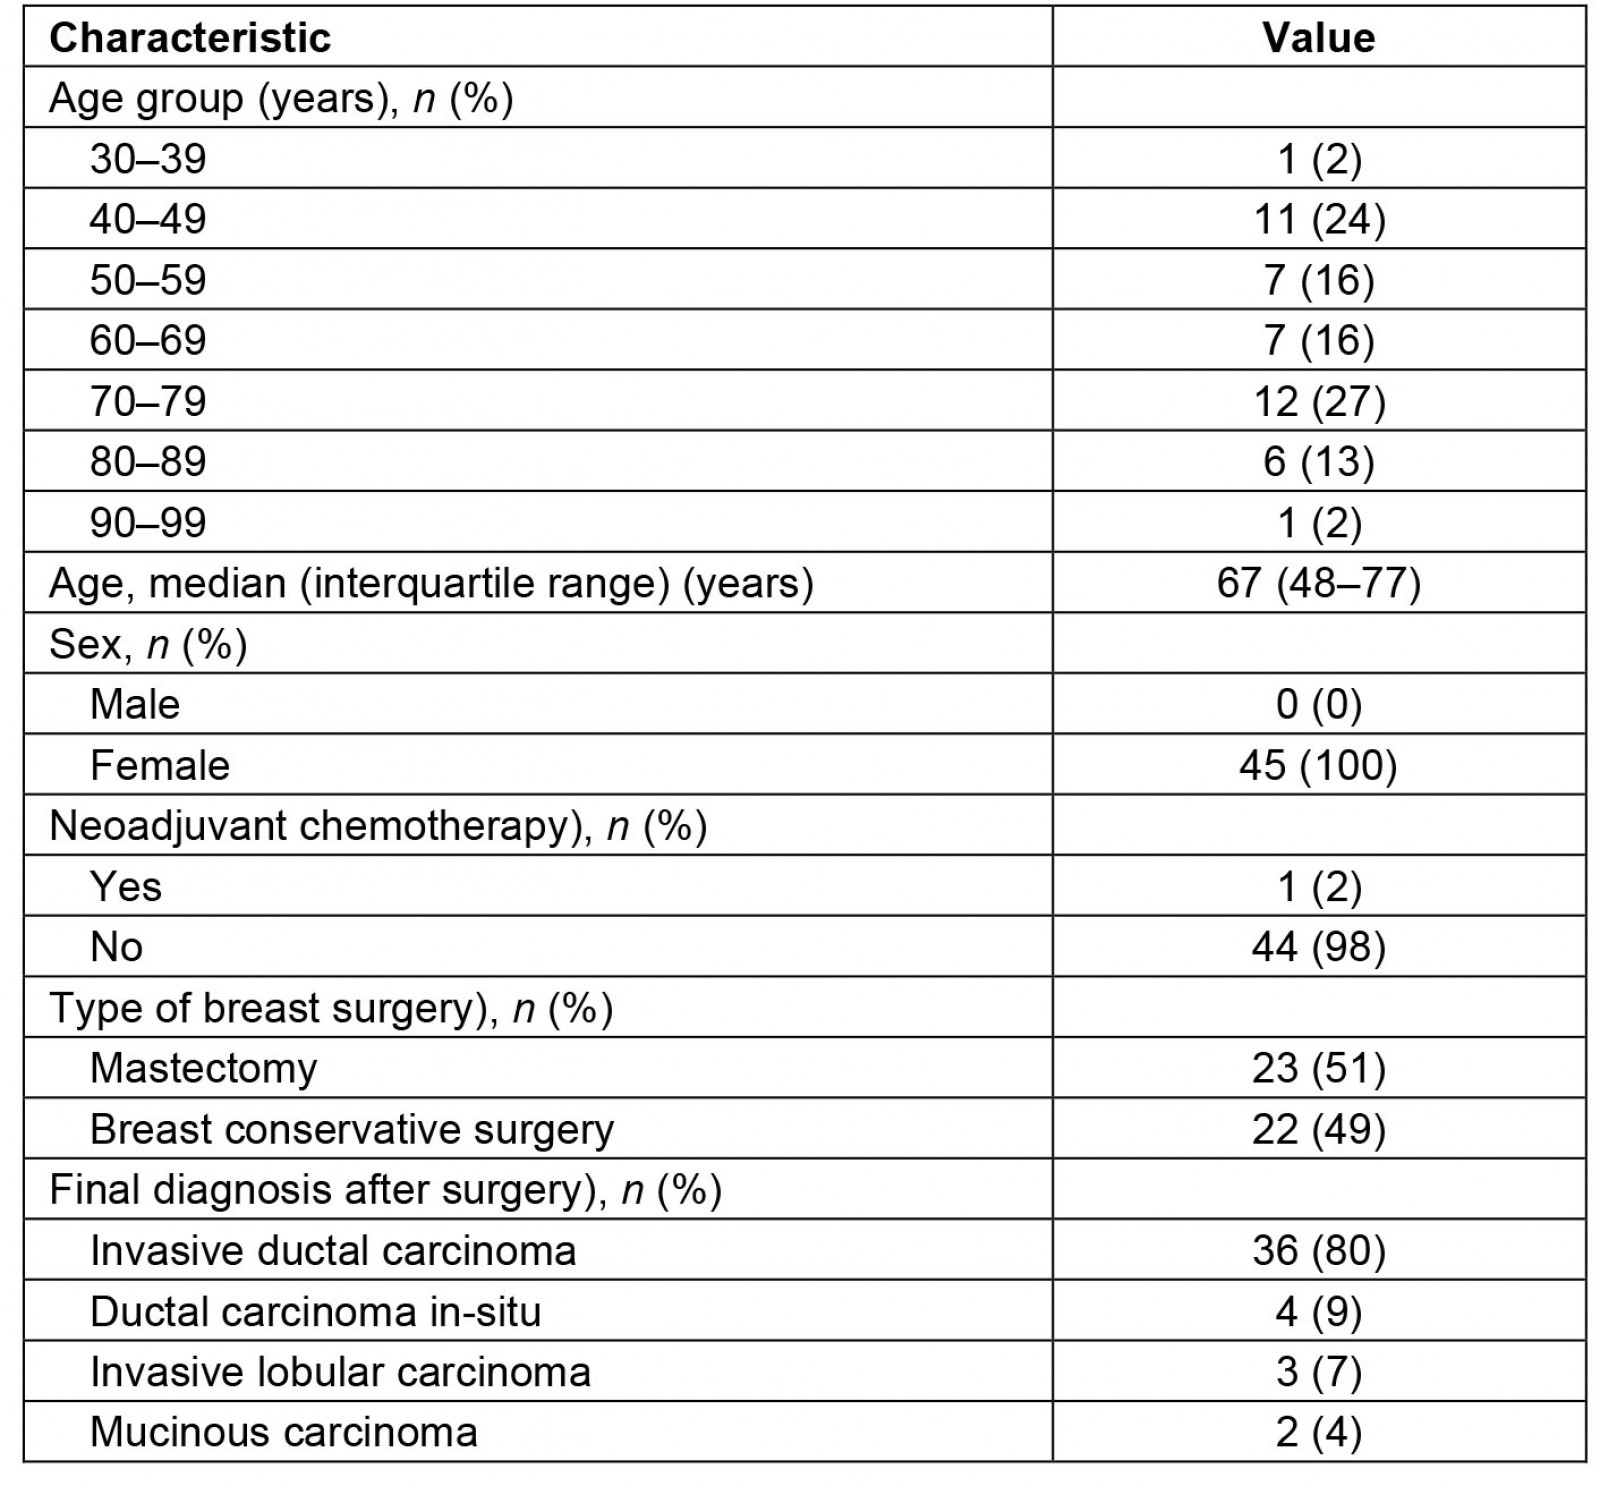

Process of pathological diagnoses, telecommunication technology and related costs

The submitted sentinel lymph nodes, in both systems, were cut at the largest cross-sectional slice for the first few times, and then at a thickness of about 2 mm in the short-axis direction. All preoperative and postoperative diagnoses using paraffin section were made by a pathologist who specializes in breast cancer pathology, visiting Jyoban Hospital once a week. Postoperative diagnoses of sentinel lymph nodes consist of not only inspections of paraffin sections but also of frozen sections made during the surgery.

Telepathology for intraoperative frozen section consultations employed one of two distinct types of telecommunication technology, depending on availability: a cloud-based system (responsibility of Medical Network Systems, MNES) or a simultaneous videoconferencing system (responsibility of Iwaki City Medical Center, ICMC).

For the cloud-based system, we created digital slides for frozen sections of sentinel lymph nodes using the digital scanner Nano Zoomer S210 (Hamamatsu Photonics; https://www.hamamatsu.com/jp/ja/product/life-science-and-medical-systems/digital-slide-scanner/C13239-01.html), which allows a magnification of 80 times at maximum, and uploaded them to the server. This is one of the few systems eligible for reimbursement under the Japanese national health insurance scheme and is considered to enable a comprehensive slide examination of the slides through digital imaging, ensuring a diagnosis that is on par with the traditional pathological diagnosis conducted using a microscope. However, the system may present difficulties in easily focusing on slides with significant thickness.

Pathology diagnoses were made using the viewing software LOOKREC (MNES Inc.; https://mnes-lookrec.com), which allows a magnification set by a digital scanner at maximum.

Eye Vision NEO (ENWA; https://www.enwa.tv/eyevision-neo) was used as the videoconferencing system, cellSens Standard (Olympus; https://www.olympus-lifescience.com/ja/software/cellsens) as microscope image viewing software, and SS-VPN (Shonan Tech, Kanagawa, Japan) as the virtual private network line, specifically prepared for the ICMC and Jyoban Hospital to connect the two hospitals.

The costs of the systems are shown in Table 1. Other details of intraoperative frozen section consultations using telecommunications technology are summarized in Supplementary text 1.